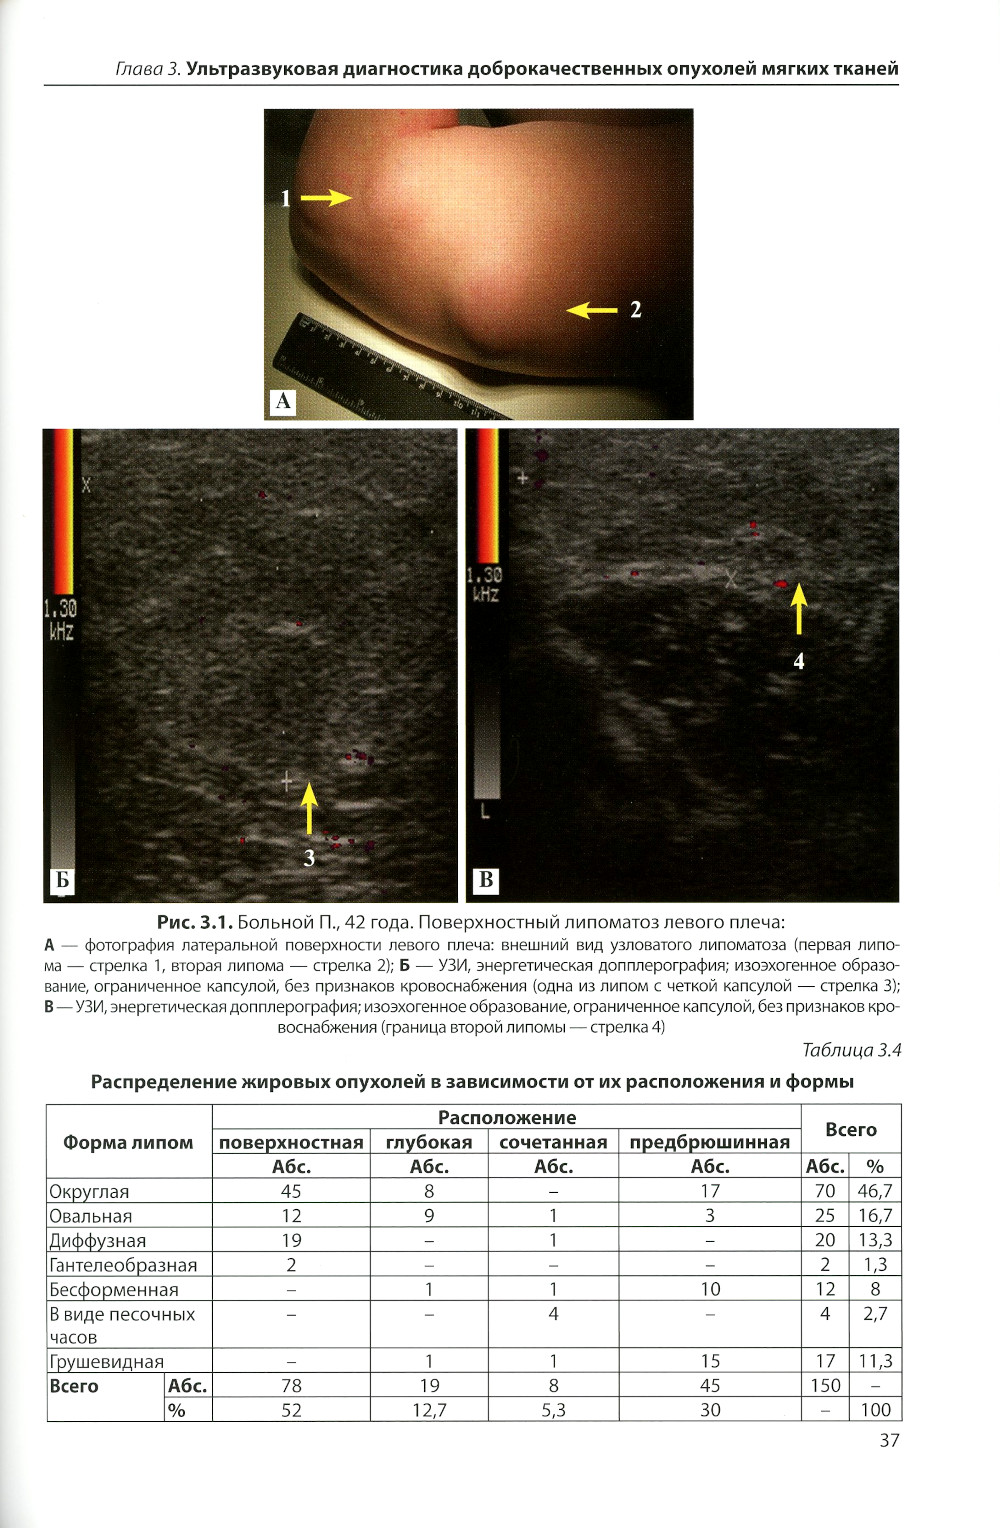

Опухоли мягких тканей - один из труднейших разделов клинической и морфологической визуализации. Цель исследования: улучшение лучевой диагностики опухолей и опухолевидных образований мягких тканей путем выполнения комплексного УЗИ. Основой научного исследования послужили результаты анализа данных клинического и лучевого обследования 433 больных опухолями и опухолеподобными образованиями мягких тканей. Детально описана УЗ-семиотика этих заболеваний при их визуализации в В-режиме. Показана диагностическая эффективность изучения степени кровоснабжения различных образований с помощью допплерографии. Разработаны дифференциально-диагностические критерии оценки результатов эластографии в определении наличия истинной опухоли и возможной ее злокачественности. Определена высокая диагностическая точность разработанного комплекса УЗ-методик (около 90%). Необходимой частью комплексного обследования должно быть проведение пункционной биопсии образований под контролем УЗИ. Создан алгоритм применения комплекса ультразвуковых и других необходимых лучевых исследований. Обосновано большое значение результатов комплексного УЗ-обследования для определения показаний к оперативному лечению больных в условиях дневного стационара в рамках актуальной концепции «стационарозамещающих» технологий. Результаты научного исследования могут быть использованы в практической работе врачей дневных стационаров, поликлиник, амбулаторных центров, а также в учебной работе кафедр амбулаторной хирургии, лучевой диагностики.| Издательство | Элби |